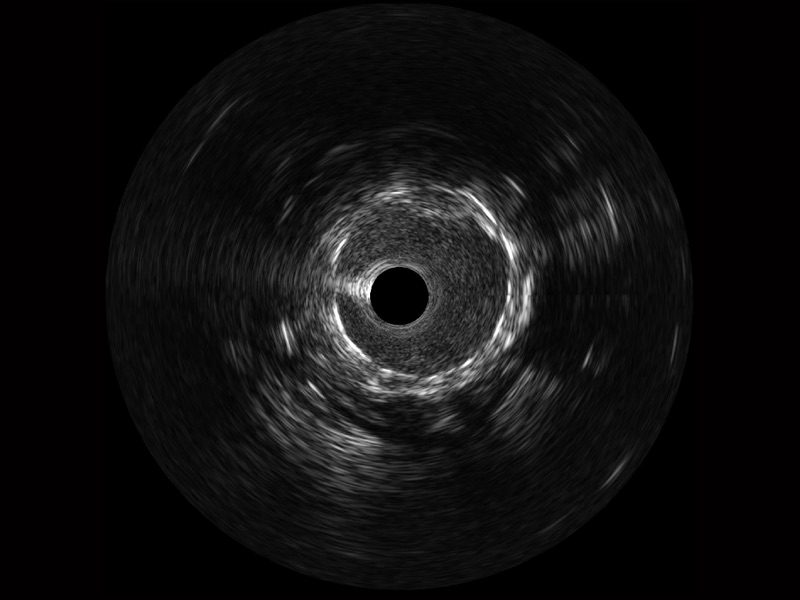

milan米兰宽频IVUS图像

对比传统IVUS导管成像,milan米兰宽频IVUS图像的近场支架梁显影更细腻,远场中膜外血管仍清晰可辨,兼顾远中近,兼顾分辨力与穿透深度